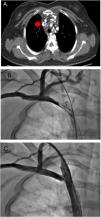

Intracranial hypertension due to central venous stenosis (CVS) is an under-recognized but potentially morbid complication of central venous catheters that can have a benign course if recognized and treated early. Here we report a case of a 23-year-old woman requiring hemodialysis via right subclavian catheter who presented with an intracranial hypertension syndrome and sudden visual loss secondary to right innominate vein thrombosis that improved after angioplasty treatment. This case illustrates how CVS can alter the pressure gradient between the subarachnoid space and the cerebral venous sinuses by increasing venous pressure, affecting cerebrospinal fluid drainage. Since CVS is a common finding in patients receiving hemodialysis, intracranial hypertension due to central venous stenosis is a differential diagnosis to consider in patients of this type who present with intracranial hypertension syndrome.